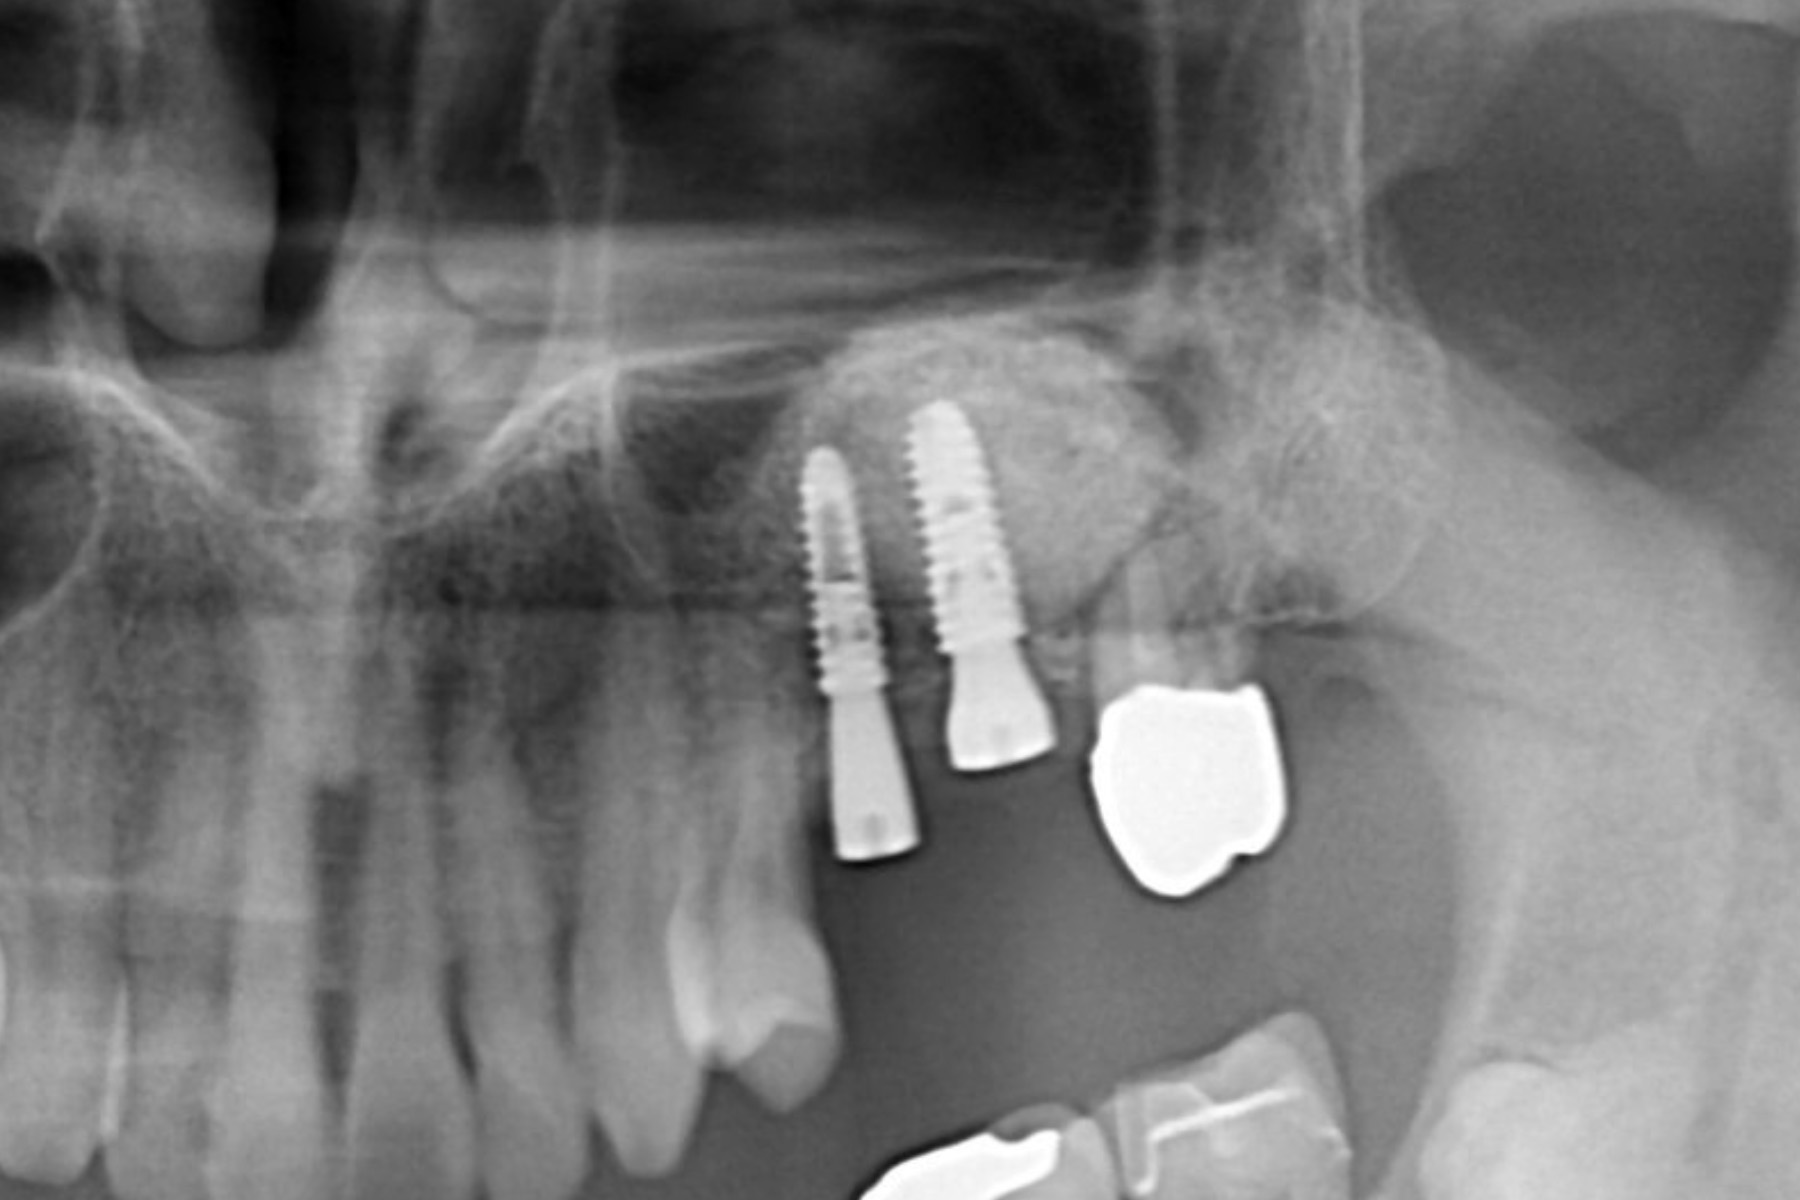

| 主訴 | 他院で骨が薄くインプラントは出来ないと言われた。 |

| 治療内容 | インプラント埋入手術を行うには骨が5mm程しかなく不可能な状態であった。その為骨を中規模に造成しインプラント埋入手術を行えるようにした。加えて患者負担を軽減する為に同日に骨造成手術とインプラント埋入手術を行い手術も1度で済んだ。 |

| 治療期間 | 3〜4ヶ月 |

| 治療費 | 骨造成手術:150,000 インプラント埋入手術:¥300,000 |

| 治療リスク | 術後疼痛、腫脹、必要であれば追加の処置を伴うこともある。 |